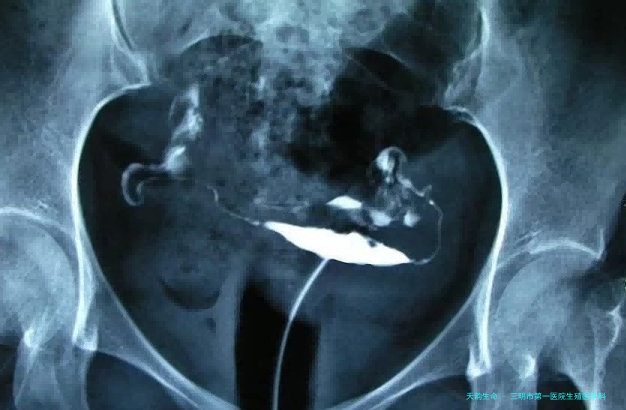

子宫输卵管造影 经阴道彩超卵泡监测